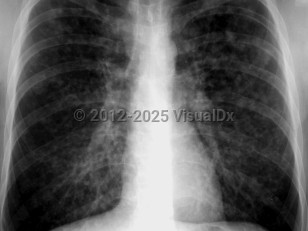

Acute respiratory distress syndromeAcute respiratory distress syndrome

Pulmonary edema

Community-acquired pneumonia